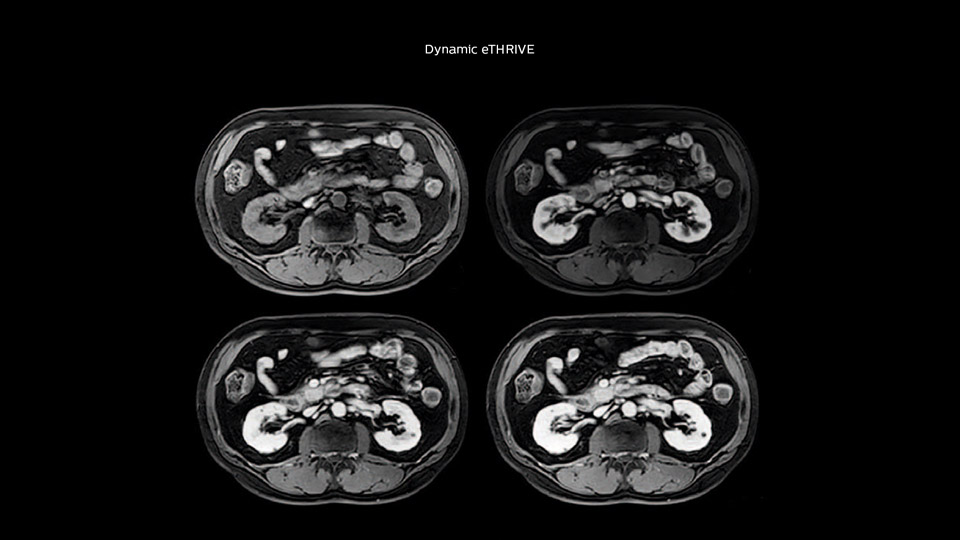

Comparison of liver MRI with and without MultiVane XD motion correction

In this example the image quality of the MultiVane XD images is evidently better than in the images without MultiVane XD. Ingenia 1.5T with dS Torso coil solution.

“We acquire one transversal high resolution T2-weighted sequence with 3 mm slice thickness, for example for pancreas or liver lesions. Then we also add a T2 fat suppressed MultiVane XD SPIR sequence. We perform these two routinely in our liver imaging. We use high dS SENSE factors to significantly shorten scan times to 2-4 minutes, which can improve our protocol; it’s a very robust scan.”

“We include mDIXON for the dynamic sequences because of the robust and homogeneous fat suppression we get with that. We had been using eTHRIVE, but we are now quite happy with mDIXON. Sometimes we use a medication to calm the bowels, to further improve the image quality.”